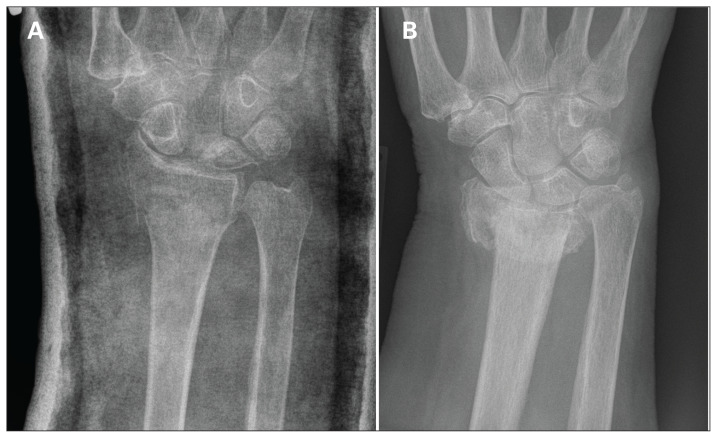

Fig. 5.

Radiographs associated with the lowest and highest standard deviations for measurements of radial inclination. (A) Radiograph 27 was associated with the lowest variation (i.e., it was the easiest to interpret). (B) Radiograph 1 was associated with the highest variation (i.e., it was the most challenging to interpret).